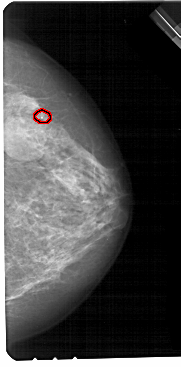

FILE: A_1705_1.RIGHT_CC.OVERLAY

TOTAL_ABNORMALITIES 1

ABNORMALITY 1

LESION_TYPE CALCIFICATION TYPE PLEOMORPHIC DISTRIBUTION CLUSTERED

ASSESSMENT 4

SUBTLETY 2

PATHOLOGY BENIGN

TOTAL_OUTLINES 1

BOUNDARY